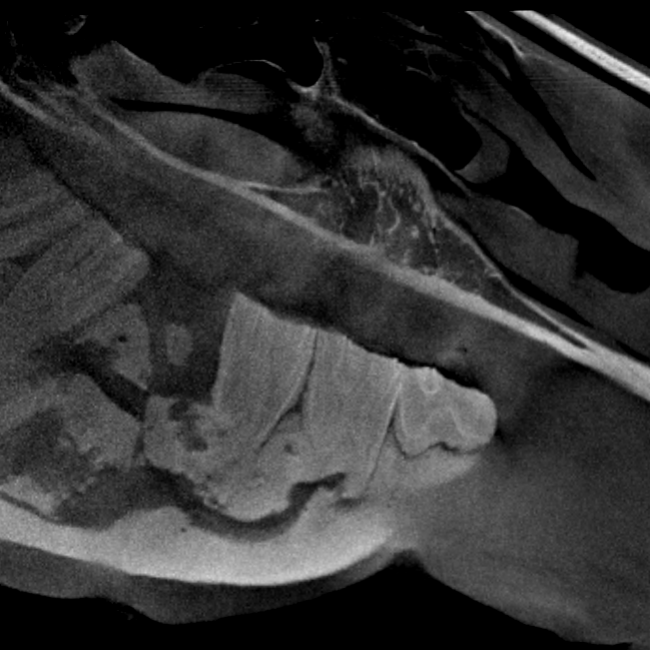

Our High Definition Volumetric Imaging (HDVI) technology represents the most advanced stage of Flat Panel CT technology. It offers exceptional diagnostic imaging for both hard and soft tissues, in diagnostic settings and intraoperative theaters. It is the gold standard for orthopedic applications.

Pegaso enhances safety and usability by enabling the scanning of a standing horse’s head, neck, and limbs.

Scan of the standing horse

Pegaso scans head, neck and limbs of the standing horse